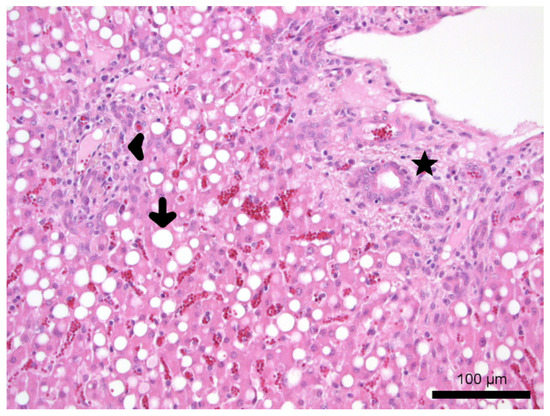

3.3.3. Post Mortem Investigation